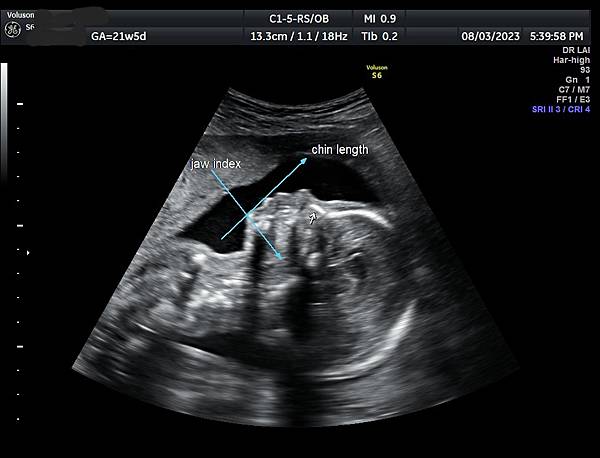

孕兒診所賴錫鉅醫師 414 ‘’如果合併小下巴,我們需要慎重的考慮未來‘’ : 下巴指數 jaw index 經驗分享

‘’如果合併小下巴,我們需要慎重的考慮未來‘’

下巴指數 jaw index 經驗分享